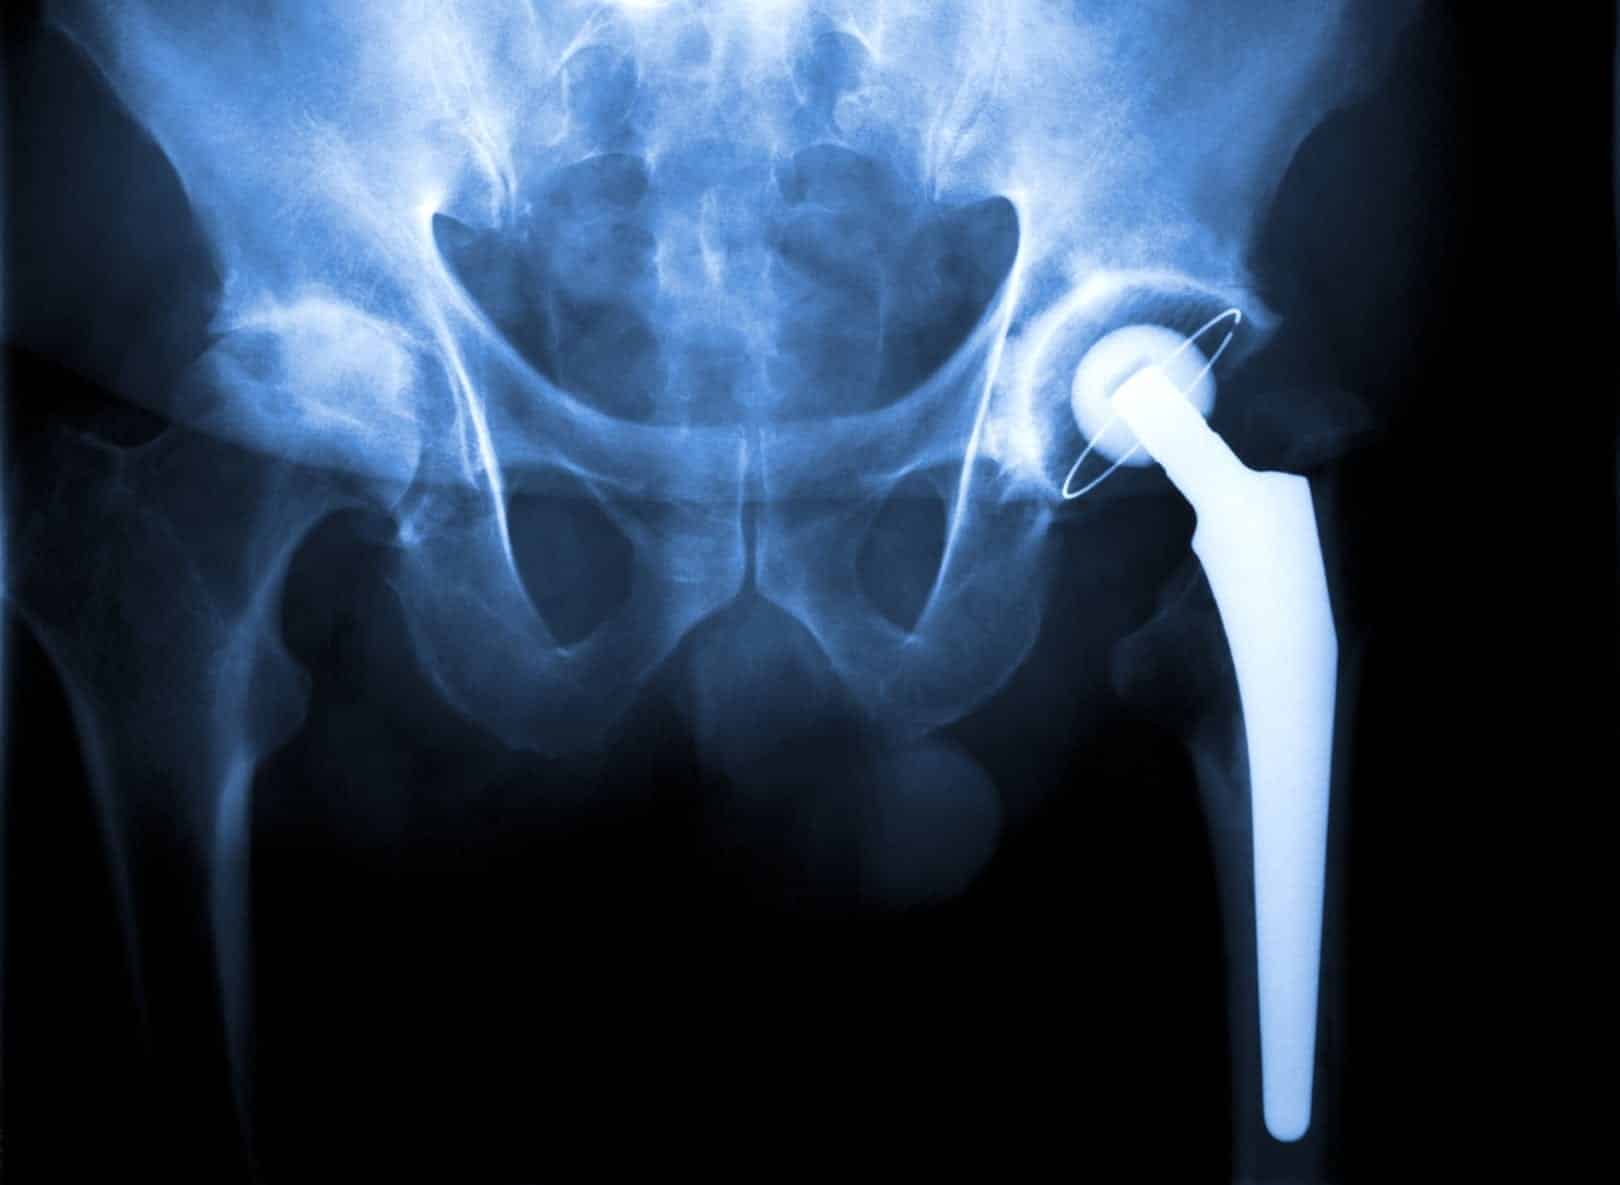

In 2006, Christiansen received a Wright hip replacement expected to last between 15 and 20 years. Only six years later, her metal-on-metal implant had to be surgically removed when it loosened and became dislodged, causing severe pain and other complications. When the implant was removed in 2012, the surgeon noticed inflammation of the membrane lining the joint, and signs of metal poisoning within the joint itself.

The nearly 550 Wright hip replacement lawsuits currently pending in federal district courts have been consolidated in an MDL in Georgia. The MDL, which was established in 2012, claims that a defective or unreasonably dangerous design is to blame for the failure of the hip implant. Wright Medical is facing lawsuits over three products in total, the CONSERVE Total-A-Class Advanced Metal Hip Implant System, the CONSERVE Total Hip Implant System, and the CONSERVE Resurfacing System. To date, there have been no recalls issued for any of these products, however, more than 200 adverse reports related to similar metal hip implants have been received by the FDA.

In addition to inflammation, metal poisoning, and the potential need for removal, complications linked to the Wright hip replacement systems include severe pain, the shedding of debris into tissue and the bloodstream, and disability. Several lawsuits claims that pieces of metal have migrated into the tissues surrounding the implant, resulting in blood poisoning, swelling, and extreme pain.